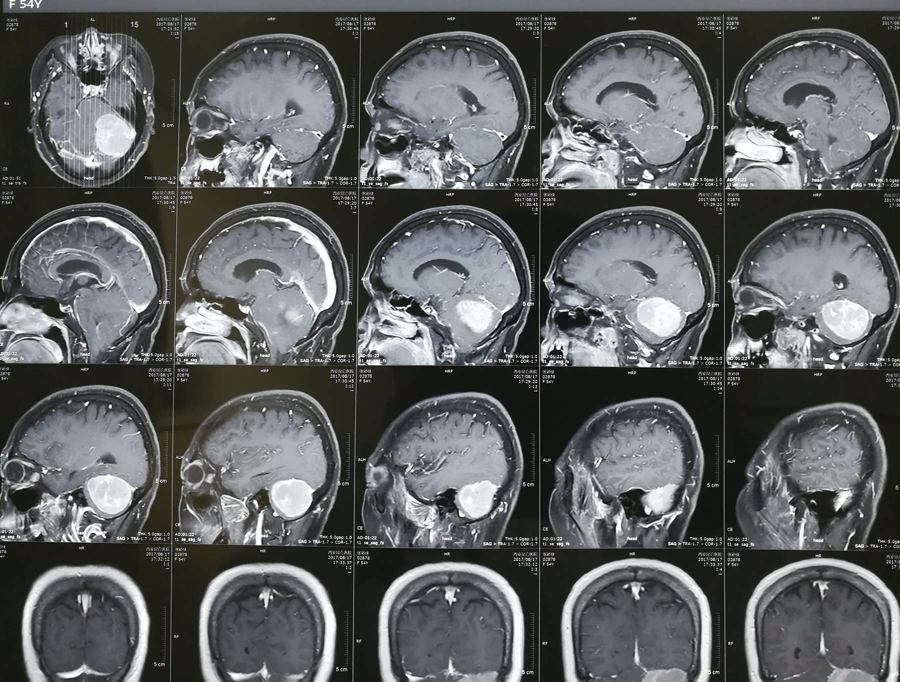

腦膜瘤

小腦腦膜瘤嚴重嗎?出國治療腦膜瘤哪個醫(yī)院好?

小腦腦膜瘤嚴重嗎?出國治療腦膜瘤哪個醫(yī)院好

小腦腦膜瘤嚴重嗎? 出國治療腦膜瘤哪個醫(yī)院好?2018年的哈爾濱市新陽路小學五年二班的班主任(邰慧老師)被診斷為腦膜瘤,在治療時需要剃掉頭發(fā),隨后當老師治療完歸來時,27個男...